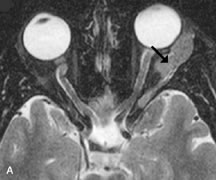

PATIENT PREPARATION Before MRI is performed, patients must be screened and prepared to avoid the potential hazards associated with the strong magnetic field. Patients who have ferrous aneurysm clips or cardiac pacemakers, who depend on life-support equipment, or who retain a possible metallic intraocular foreign body are not candidates for this imaging modality. MRI cannot be performed on obese patients who cannot fit into the bore of the magnet. Patients who are claustrophobic may not tolerate a prolonged period of study within the confines of the magnet, whereas others might do well if given a mild sedative. All worn metallic objects (e.g., necklaces, watches) should be taken off, credit cards set aside, and eye makeup removed before entering the room containing the magnet.5,20,34,35,36 NORMAL ORBITAL ANATOMY T1-weighted images provide the best anatomic details of the orbit because they display superior contrast resolution between normal structures (see Fig. 8). The vitreous has a long T1, resulting in an intermediate signal similar to brain, whereas the crystalline lens and sclera appear dark because of a longer T1 and short T2. The extraocular muscles, like all skeletal muscles, demonstrate a moderately long T1 and short T2 and highly contrast with the intense signal of the surrounding orbital fat (adipose tissue has an extremely short T1). The lacrimal glands appear as mottled areas of reduced intensity of the signal from the orbital fat in the lacrimal fossa. The optic nerves are seen with the same signal intensity as brain white matter and are hypointense relative to the orbital fat because their Tl is longer than the Tl of fat but shorter than the Tl of water. Cortical bone is not well delineated because it contains little free water, yielding minimal signal in MRI, and thus appears dark on all pulse sequences. This feature explains why MR images of the orbital apex and intracanalicular portion of the optic nerves are superior to comparable CT scans. Partial volume averaging of the bones in these regions obscures soft tissue details on CT images, whereas MRI reveals the signals only from the soft tissue structures with no cortical bone input. Bone marrow, on the other hand, is seen as a relatively intense signal because of its high fat content (see Fig. 8).37,38 T2-weighted pulse sequences are not ideal for imaging normal anatomy; however, they are particularly useful in revealing pathologic conditions (see Fig. 9). T2-weighted studies are most easily recognized by a bright vitreous signal. ORBITAL DISEASES Vascular Lesions Cavernous hemangiomas appear as well-circumscribed, smooth, usually intraconal masses that are isointense to muscle on T1-weighted images and hyperintense on T2-weighted images (Fig. 12). Patchy early enhancement is typically followed by diffuse, more homogeneous enhancement.39 The internal architecture of the mass, including septation and internal vasculature, may often be appreciated with high-quality orbital imaging.40 Lymphangiomas consist of ectatic vascular channels within a connective tissue stoma with varying degrees of lymphoid cellularity. On MRI, these tumors are typically poorly circumscribed, multicompartmental, and heterogeneous, often showing cystic dilations with fluid levels (Fig. 13). The signal characteristics within lymphangiomas vary considerably, reflecting cystic and solid components and the varying paramagnetic characteristics of blood at different stages of degradation.40–42 Acute hemorrhage appears hypointense on both T1- and T2-weighted formats. Methemoglobin present in subacute hemorrhage (3 to 14 days) leads to hyperintense signal on both T1- and T2-weighted images.41 A small percentage of lymphangiomas appear radiologically indistinct from orbital cavernous hemangiomas.43 Orbital varices are venous malformations that expand with increased systemic venous pressure, such as with Valsalva maneuvers. Because rapid acquisition of images during a Valsalva maneuver is important in imaging such a lesion, conventional or spiral CT is currently the modality of choice.44 MRI is an excellent modality for demonstrating enlargement of the cavernous sinus and dilation of the superior ophthalmic vein in patients with high-flow carotid-cavernous fistulas (Fig. 14).37MRA may be helpful in the evaluation of the venous outflow pattern. The rapidly flowing blood in these vascular structures carries the excited protons out of the section before they can be imaged, resulting in their dark appearance.5 In low-flow dural arteriovenous malformations, MRA may help define the arterial feeding vessels.45 Neural Lesions MRI is more effective than CT in delineating the intracranial optic nerves, chiasm, and optic tracts and, for this reason, is the preferred imaging modality in the evaluation of optic nerve disorders. The spatial relationships and image contrast of the orbital tissues with intraorbital optic nerve tumors is comparable between the two imaging modalities. The normal nerve is isointense to brain and appears enlarged and kinked owing to infiltration of an optic nerve glioma on T1-weighted images. Gliomas appear hyperintense on T2-weighted images and may be heterogeneous owing to cystic areas within the tumor. Contrast enhancement is variable.46 Intraorbital and intracranial optic nerve sheath meningiomas are usually isointense to cortical gray matter on Tl-weighted images and remain isointense on proton density studies (Fig. 15). Gd-DTPA is useful in delineating the intracranial extension of optic nerve meningiomas.7,47 The hyperostosis of bone and calcification associated with meningiomas are not demonstrated as well on MRI studies as on CT scans.20,37 Gd-DTPA–enhanced MRI also appears promising in the study of the permeability of the blood–brain barrier in selected optic neuropathies.22,48 MRI may reveal an enlarged optic nerve and some degree of contrast enhancement in cases of optic neuritis.49 Muscle Disorders Extraocular muscle enlargement in patients with thyroid-associated orbitopathy is demonstrated equally well with CT and MRI studies. However, the superior tissue contrast on MR images reveals better details of the relationships of the optic nerve to the thickened muscles at the orbital apex (Fig. 16).50 In addition, MRI may be able to differentiate between muscles that are enlarged as a result of edema and active inflammation and those enlarged because of fibrosis by their T2 relaxation times.21 Quantitative MRI was not found to be accurate in predicting the success of low-dose orbital irradiation.51 However, a muscular index relating the diameters of the rectus muscles to the bony orbital dimensions was useful in predicting optic nerve compression.52 MRI is also effective in imaging orbital tumors of mesenchymal origin, such as rhabdomyosarcoma, particularly in the assessment of extension into the anterior and middle cranial fossae (Fig. 17).37 The lack of any pathognomonic radiologic features necessitates rapid orbital biopsy when rhabdomyosarcoma is suspected. Osseous Lesions In general, CT is the imaging modality of choice when details of quantity and quality of bone are needed; however, abnormalities of bones can be detected indirectly by MRI. Cortical bone appears black (signal void) on MR images because of its low proton density and free-water content. The absence or discontinuity of the signal void of the orbital walls may represent bony destruction or fracture. Hyperostosis associated with prostate metastases or meningioma is visualized as areas of black smudging.50,53 Diseases in which the bone is replaced by pathologic tissues with a high free-water content, such as fibrous dysplasia, are well demonstrated on MRI. An intermediate signal intensity on T1-weighted images and hypointense signal on T2-weighted images is representative of fibrous dysplasia. Enhancement on post–Gd-DTPA MR scans is seen and is more evident in areas that are less mineralized.54 Cystic Lesions Dermoid cysts appear as rounded, well-defined lesions typically contiguous with an orbital bony suture. The high-intensity signal on T1-weighted images is attributed to the sebaceous-produced lipid contents (Fig. 18).31,50 Mucoceles may demonstrate a hypointense or hyperintense signal on MR images, depending on the concentration of proteinaceous or inflammatory fluid components. The integrity of the bony walls of the expanded sinus cavities cannot be assessed on MR as well as by CT.37,50,55,56 A high-signal intensity on Tl- and T2-weighted images is characteristic of orbital chronic hematic cysts because of the blood-breakdown products within the cysts.57 Trauma Although soft tissue relationships are usually better demonstrated on MRI, the evaluation of craniofacial bony trauma is preferable with CT. For example, prolapse of orbital fat through a fracture site and hemorrhage of adjacent tissues are demonstrated in an MR image, but the actual fractured bone is not imaged. Three-dimensional MRI of the orbit in subacute trauma has been described,58 although its precise role is not currently established. MRI has been suggested to be superior to CT in detecting intraorbital wooden foreign bodies.59,60 In a series of penetrating orbital injuries with organic foreign bodies, however, MRI was able to identify the foreign body in only four of seven cases.61 With an in vitro model for wood foreign body, McGuckin and colleagues concluded that CT was the imaging modality of choice.62 A careful history and, in selected cases, plain films to rule out a metallic foreign body are crucial before MRI is considered in patients with periocular trauma. MRI is particularly helpful in the detection and characterization of subperiosteal hematomas of the orbit (Fig. 19). They are most commonly seen in the subperiosteal space of the superior orbit as well-defined masses following a traumatic injury. The signal intensity varies depending on the acute, subacute, or chronic nature of the hematoma, based on the stage of blood degradation. Fresh hemorrhages are hypointense on T1-weighted images and hyperintense on T2 images. Hematomas that are 1 to 7 days old are hypointense on both T1- and T2-weighted images. T1-weighted images of hematomas more than a week old are hyperintense due to the oxidation of deoxyhemoglobin to methemoglobin, whereas the T2 images remain hypointense.63 Metastatic Tumors Breast carcinoma metastatic to the orbit has been demonstrated to be hypointense to the surrounding orbital fat on T1-weighted studies and hyperintense on T2-weighted images and has an affinity to the extraocular muscles (Fig. 20).50,64 The MRI characteristics of prostate carcinoma metastatic to the orbit have been described as involving the greater and lesser wing of the sphenoid, orbital roof, and optic canal. Diffuse bone hypertrophy with isointense or slightly hyperintense tissue on T1-weighted images represents the osteoblastic carcinomatous bone infiltration. Contrast enhancement is variable on T1-weighted and fat-suppressed images.65 Most other metastatic tumors also have a lower intensity signal on T1-weighted images and appear to displace or infiltrate normal orbital structures; however, their signal characteristics are variable on T2-weighted MR images.66 Many metastatic tumors demonstrate bright contrast enhancement with Gd-DTPA. Infectious Disorders MRI findings of preseptal and orbital cellulitis typically include increased signal intensities on T2-weighted images of the eyelids and orbital fat, respectively, due to the increased water content of the tissues. Since most cases of bacterial orbital cellulitis are associated with paranasal sinusitis, hyperintense signals of the affected sinuses may also be found on T2-weighted images as well as enhancement of polyps and granulation tissue on postgadolinium T1-weighted MR images. Subperiosteal abscess formation may occur due to contiguous spread of infection from the paranasal sinuses and appear on MRI as an area of intermediate signal on T1-weighted and proton-weighted MR images. The abscess may appear slightly hyperintense compared with muscle on T2-weighted scans with the necrotic contents having the greatest intensity.67 MRI and MRV are more sensitive than CT in revealing cavernous sinus thrombosis. Engorgement of the cavernous sinus, extraocular muscles, and ophthalmic veins is seen with hyperintensity of the thrombosed sinuses evident on all pulse sequences. The enlarged, thrombosed superior ophthalmic vein appears less hypointense than the normal contralateral ophthalmic vein, and hyperintensity within the lumen of the vessel may be seen on T1- and T2-weighted MR images.68 Inflammatory and Lymphoproliferative Lesions Inflammatory conditions of the orbit, both idiopathic (inflammatory pseudotumor) and those of known causes, have been found to be hypointense to fat and isointense to muscle on Tl-weighted studies and isointense or slightly hyperintense to fat on T2-weighted images (Fig. 21).50,64,69 The more fibrous or sclerosing varieties have less signal intensity on T2-weighted images. Marked enhancement is seen in pseudotumor infiltrates after gadolinium administration.70 The same signal characteristics are demonstrated in patients with Tolosa-Hunt syndrome, with mass lesions seen in the cavernous sinuses and orbital apices.71 Lymphomas have MRI characteristics similar to those of inflammatory lesions in that they are hypointense to fat and isointense to muscle on T1-weighted images (Fig. 22). They may appear hyperintense to fat on T2-weighted images, perhaps owing to less fibrosis than that seen in orbital inflammatory pseudotumor, although this is not a consistent finding.31,50,66 Lymphoid tumors typically enhance moderately after contrast injection. Unfortunately, studies have shown that tumor density and homogeneity are similar between inflammatory and malignant orbital infiltrates, and MRI cannot differentiate these lesions.72,73 Lacrimal Gland Tumors Lacrimal gland lesions present special problems in diagnosis and management. Pleomorphic adenoma (benign mixed tumor) should not be biopsied, but rather excised in toto. On the other hand, for lymphoma and inflammatory infiltrates, incisional biopsy is more appropriate than complete excision of the lacrimal gland. Thus, preoperative clinical and radiologic evaluation are especially crucial in planning appropriate surgical management. Pleomorphic adenomas demonstrate long T1 and T2 signal characteristics. They may show heterogeneity on T2-weighted images74 and moderate to marked enhancement with contrast.75 Signal characteristics of adenoid cystic carcinoma include hypointensity to fat on T1-weighted images, hyperintensity to fat with increased T2 weighting, and isointensity to fat on proton density-weighted studies (Fig. 23).31,75 Secondary bony alterations of the lacrimal fossa associated with lacrimal gland tumors, such as remodeling (benign mixed tumor) or destruction (adenoid cystic carcinoma), are seen indirectly on MR images; however, bone windows on CT scans provide better delineation of these changes. In contrast to the round or globular appearance of benign or malignant epithelial tumors of the lacrimal gland, lymphoproliferative tumors usually appear to be molding or draping onto the globe and the surrounding bony orbit. LACRIMAL DRAINAGE SYSTEM DISORDERS MRI with surface coils provides excellent spatial resolution and tissue-specific signal intensities of the lacrimal drainage system. These parameters have been found useful to more accurately demonstrate the extent of lesions in the lacrimal sac and differentiate long-standing mucoceles from solid tumors than CT.76 Physiologic studies in patients with tearing disorders now include MR dacryocystography, in which Gd-DTPA is either placed topically in the conjunctival fornix or injected by cannulation into the lacrimal sac. They provide a detailed morphologic and functional analysis of the lacrimal excretory system; however, they are no more sensitive than digital-subtraction dacryocystography or CT dacryocystography.77–79 INTRAOCULAR TUMORS On MRI, uveal melanomas have a typical appearance that helps to differentiate them from other primary and secondary intraocular tumors as well as choroidal detachments. Pigmented melanomas are hyperintense on Tl-weighted images, hypointense on T2-weighted studies, and hyperintense on proton density–weighted examinations (Fig. 24).30,31,50,80–82 These signal characteristics have been attributed to the paramagnetic properties of melanin because of stable free radicals that shorten the T1 and T2 relaxation times. Moderate enhancement is seen on postgadolinium T2-weighted images. Gadolinium-enhanced T1-weighted images are particularly sensitive in detecting choroidal melanomas.83 MRI may be less sensitive in detecting extrascleral extension of tumor than echography performed by an experienced ultrasonographer.84 Tumors metastatic to the choroid are hyperintense on T1- and T2-weighted images.24 The signal characteristics, however, may be similar to those seen with choroidal melanoma. Choroidal hemangiomas, on the other hand, have an intermediate signal on T1-weighted sequences and become hyperintense on T2-weighted images50 as well as proton density–weighted images.81 Retinoblastomas display moderate signal intensity on T1-weighted studies and a low signal on T2-weighted images.31,80,85 Calcification can be easily detected by CT and ocular ultrasonography but is not imaged by MRI.25,50 The presence of optic nerve involvement is best evaluated by MRI. ACQUIRED ANOPHTHALMIA When an eye is removed owing to tumor or trauma, an implant is typically placed in the intraconal space. MRI may be useful in defining the size, shape, and position of such orbital implants.86 Porous hydroxyapatite or polyethylene implants are preferred by many surgeons performing enucleation or evisceration. A porous implant offers the possibility of supporting a motility coupling peg to increase the movement of the overlying prosthesis. MRI with contrast is used by some surgeons to evaluate the degree of fibrovascular ingrowth in hydroxyapatite87 and porous polyethylene88 implants prior to motility peg placement. |